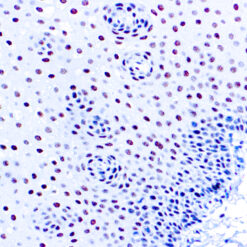

Solitary fibrous tumor (SFT) is a fibroblastic neoplasm of variable biologic potential that can arise at a wide range of anatomic sites. Almost all cases of (98%) including conventional, cellular, atypical, and malignant variants showed nuclear expression of STAT6. Staining for STAT6 was usually diffuse: 68% of cases showed reactivity for STAT6 in 75% of tumor cells. Further, the intensity of staining was strong in 67% of cases, moderate in 25%, and weak in only 7%. The heterogeneity of staining, both in terms of extent and intensity, which may be because of uneven tissue fixation or loss of antigenicity in older cases for which the unstained slides were stored for extended periods of time. All other tumor types examined were negative for STAT6, except for three dedifferentiated liposarcomas and one deep fibrous histiocytoma, which showed weak staining. STAT6 is therefore a highly sensitive and almost perfectly specific immunohistochemical marker for SFT, and can be helpful to distinguish this tumor type from histologic mimics.